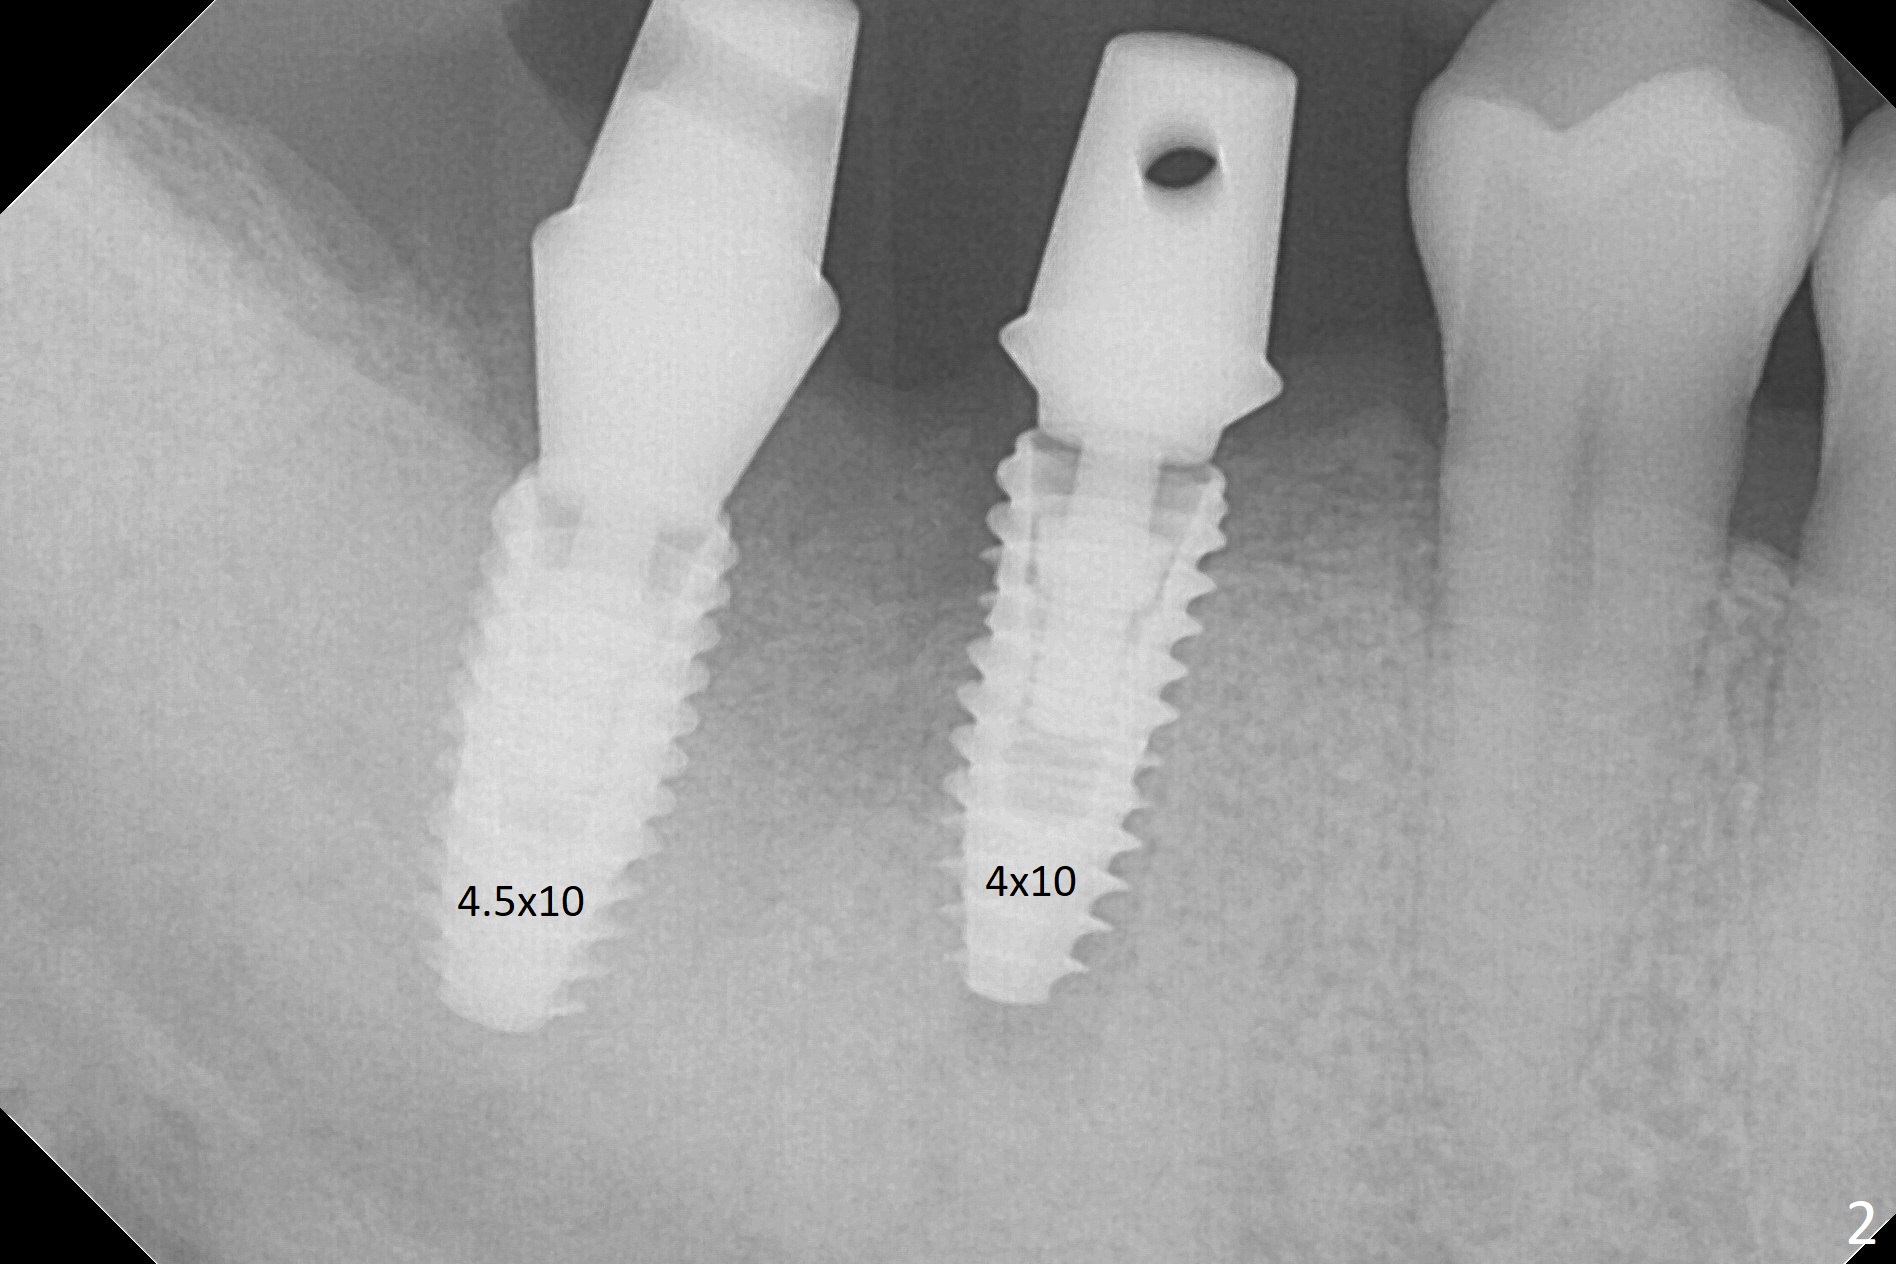

Osteotomy at the sites of #30 and 31 is initiated with Magic Split, followed by Magic Expanders (3.0 and 3.8 mm) at #31. Initial depth of osteotomy is 13 mm with 2.2 mm drill (Fig.1). After adjustment of the trajectory at #31 (Fig.1 arrow) and deepening the osteotomy by 2 mm, dummy implants are placed with stability (Fig.2). Following increase in osteotomy at #31, the larger implant in fact loses stability (Fig.3). The loose implant is pushed distal (Fig.4 arrow) with placement of autogenous bone mesial (*). The stable implant at #30 (Fig.3) and its abutment (Fig.4) are used as a post to hold periodontal dressing, which covers the wound at #31 after placement of collagen plug and suturing. In fact the same technique could be used when socket preservation was performed if an implant were placed at #30 at the same time. When the periodontal dressing dislodges, the wound at #31 heals uneventfully (Fig.5,6). The bone graft seems to remain in place 3 months postop (Fig.7). The implant is uncovered with placement of a 6.8x7 mm healing abutment 4 months postop. When a cementation abutment is placed and prepped, the buccal margin is much lower than the lingual (Fig.8 taken prior to cementation). The patient enjoys mastication with the new implant crowns 3.5 months post cementation (Fig.9).